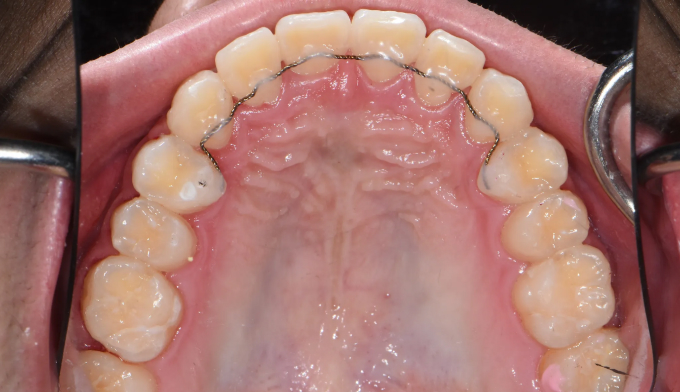

이번에는 악궁이 좁은 경우에 해당됩니다. 그 정도가 심해, 윗니 일부가 아랫니보다 안쪽으로 들어가있습니다.

상악확장장치를 통해 악궁을 넓혀주고 치아를 배열해줍니다.